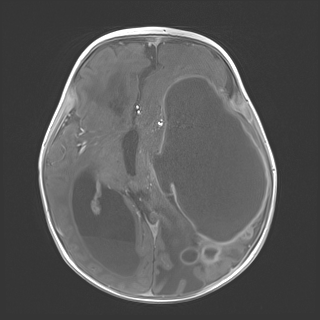

Neurosurgery was consulted, who recommended MRI and surgical management following advanced imaging. MRI revealed a large multiloculated left cerebral hemispheric abscess with marked mass effect including 1.5 cm of rightward midline shift, entrapment of the right lateral and third ventricles with associated transependymal edema, and left uncal herniation resulting in compression of the midbrain (Figure 3).

Figure 3